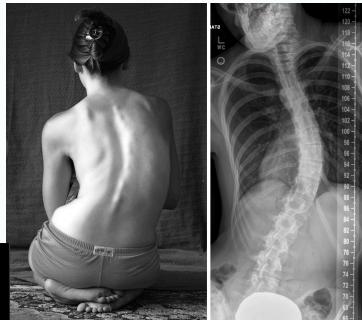

Clinical Findings

- Leaning of entire body to one side

- Head not centered directly above the pelvis

- Shoulders at different heights

- One shoulder blade more prominent than the other

- Rib cages at different heights (due to vertebral rotation)

- Uneven waist

- Raised, prominent hip

- Curve increases on forward flexion

Clinical Features

- Shoulders at different heights – one shoulder blade more prominent

- Rib cages at different heights

- Skin texture changes overlying the spine